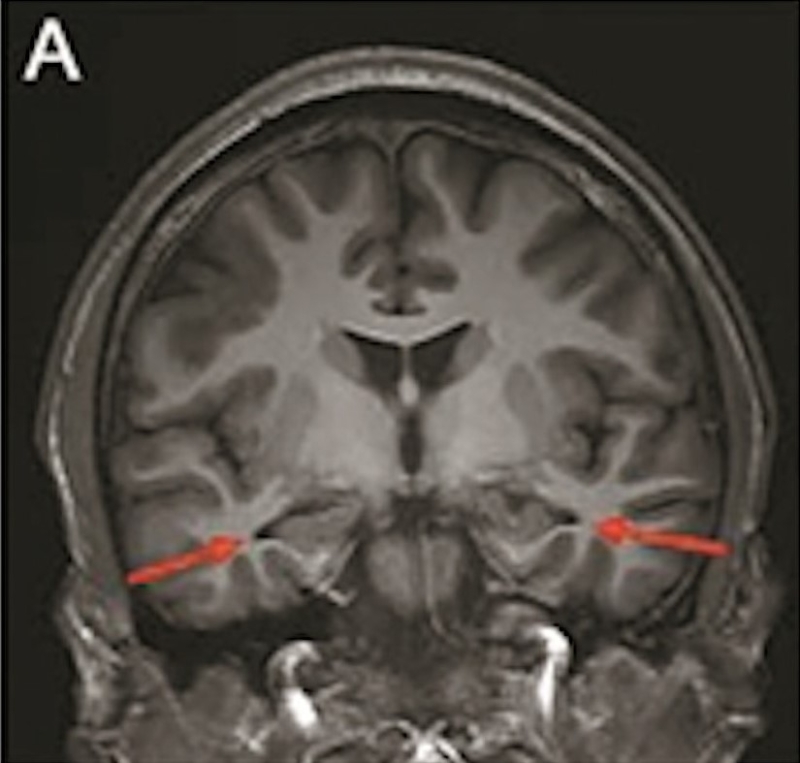

最年轻的19岁阿兹海默症男子脑部扫描结果:

▲19岁阿兹海默症(认知障碍症/脑退化症)男子脑部扫描结果。北京青年报

该名19岁男子到医院接受多项检查,包括脑脊液指标检测及正电子扫描。结果显示,他出现轻度脑萎缩等症状,最终被临床诊断为“阿兹海默症”。